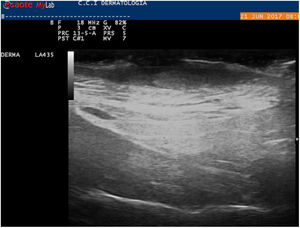

The patient was an 82-year-old man with a history of capillary malformations in the left preauricular region for which he had never been treated. He visited our department after the lesion began to bleed, resulting in the formation of a crust over the central area of the lesion. Physical examination revealed a reddish-purple tumor of approximately 5 cm with a vascular appearance. The central area of the lesion consisted of an erythematous, friable tumor of about 1 cm (Fig. 1). Skin ultrasound revealed an oval hypoechoic lesion of 47 × 4.7 mm in the superficial dermis, and an oval anechoic lesion of 8.3 × 2.2 mm on the skin surface that resulted in erasure of the epidermis with no increase in vascularization (Fig. 2). The tumor was excised respecting the margins observed on ultrasound. Histology confirmed that the lesion was a moderately differentiated squamous cell carcinoma excised with free borders (Fig. 3).

We wish to highlight the utility of skin ultrasound, which can provide important information about lesion location, size, and vascularization, as well as the relationship between the lesion and adjacent major anatomical structures.